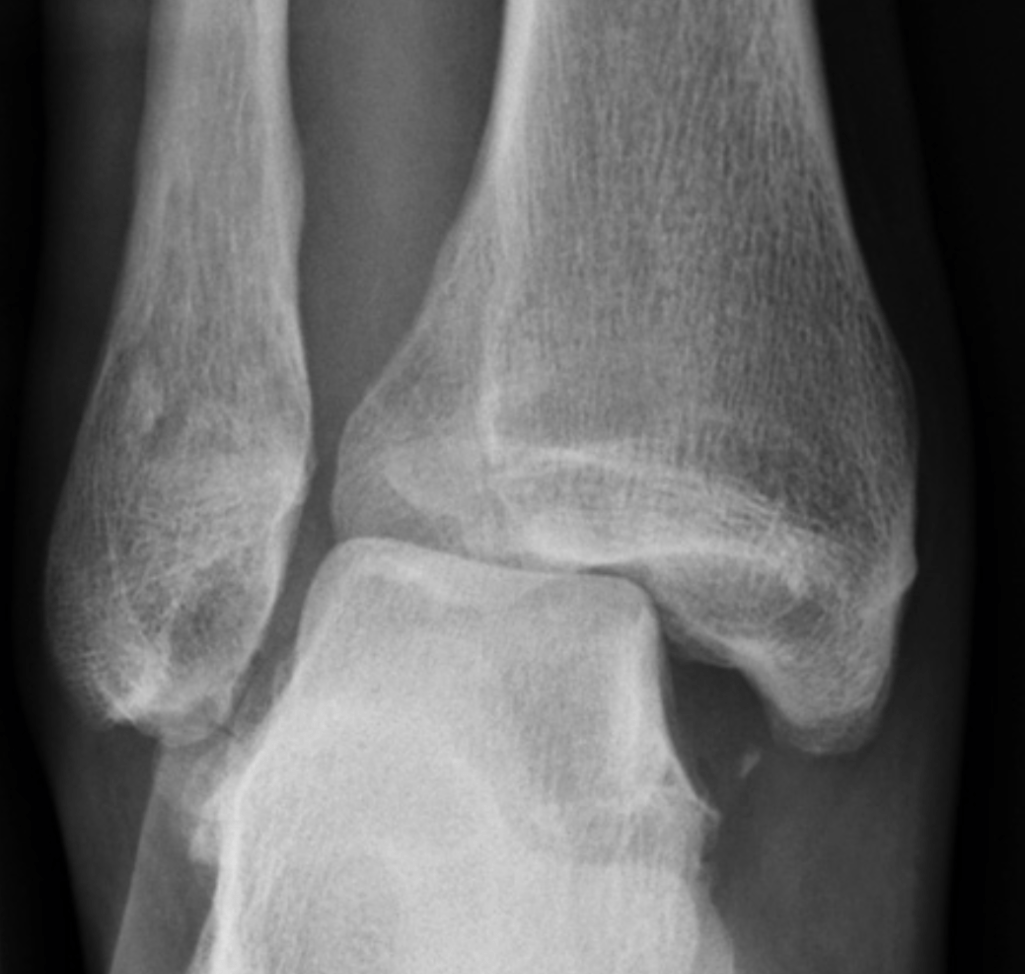

What should you suspect if you see this image?

What is Maisonneuve Fracture?

Fracture of the proximal fibula associated with injury to the medial side of the ankle and disruption of the distal tibiofibular syndesmosis.

The medial ankle injury may be either a visible medial malleolus fracture or an invisible injury of the medial ligaments.